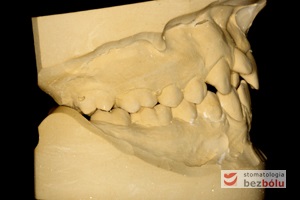

Młody 28-letni, pogodny, stale uśmiechnięty pacjent zgłosił się celem korekcji wad zębowych ograniczających pełną ekspresję uśmiechu. Głównym problemem był dodatkowy siekacz boczny (dwójka) po stronie prawej w łuku górnym. Dodatkowy ząb spowodował stłoczenia pozostałych zębów w łuku górnym oraz przesunięcie linii pośrodkowej. Obliczenia dostępnego miejsca dla siekacza bocznego wpłynęły na wybór zęba przeznaczonego do ekstrakcji. Usunięto dwójkę ustawioną dowargowo, zaś jej „siostrę bliźniaczkę” skierowaną w stronę podniebienia wprowadzono do łuku zębowego w drodze leczenia ortodontycznego. Problemem było szczelne zamknięcie szpary poekstrakcyjnej z powodu nadmiaru miejsca w kości. Wyrównano linię pośrodkową. Leczenie przeprowadzono jednym łukiem ortodontycznym górnym, dolny łuk zębowy nie wymagał założenia aparatu. Po zdjęciu zamków korekcję detali przeprowadzono z użyciem pozycjonera wykonanego w technice termoformingu. Stabilizację efektów leczenia zapewnił stały retainer klejony do powierzchni podniebiennych siekaczy górnych.